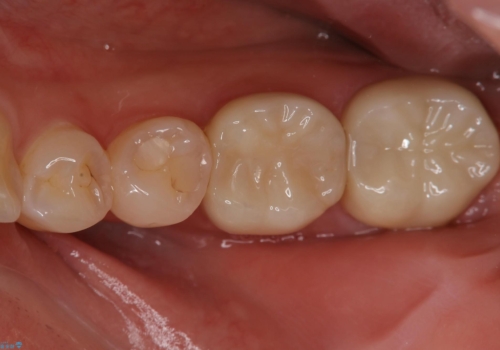

保険治療のプラスチックが劣化し虫歯に。 セラミックでつぎはぎなく治療

- 奥歯のプラスチックが劣化して二次的に虫歯ができているのを治療しました。

プラスチックがすり減り歯の高さが少ないため、薄くても丈夫なセラミックのかぶせ物(クラウン)を選びました。

本来なら骨外科といって歯周外科手術を行い歯の高さをとることが最適ですが、患者様が外科手術を希望されなかったため、なるべく外れないような形に歯の形を整えるように工夫しました。

外れないようにする工夫はほかにも連結といって2本つなげるという方法がありますが、今回は単冠といってフロスが通るように1本1本分かれた自然な形でかぶせました。

どうしても外れるようなら連結がお勧めですが、今のところ経過は良好です。